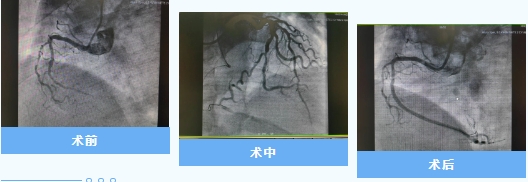

近日,兴安盟人民医院心内一科冯源海主任带领团队,成功为两名复杂冠状动脉慢性完全闭塞(CTO)病变患者实施高难度前向开通介入手术。两例手术的成功开展,标志着该院心血管介入诊疗技术取得突破性进展,为区域内复杂冠心病患者带来更优质的救治选择。

病例一患者前降支起始段完全闭塞。

病例二患者右冠状动脉远段分叉前完全闭塞,常规导丝均无法通过闭塞段,手术面临极大挑战。

冯源海主任团队结合术前影像评估,创新应用"平行导丝匍匐技术""小球囊掘进技术"及"对侧造影实时引导"等前沿策略。术中通过微导管精准操控导丝穿透致密病变,反复验证导丝真腔位置,辅以切割球囊扩张优化支架植入条件,最终成功开通闭塞血管,恢复TIMI3级前向血流。术后患者胸痛症状显著缓解,恢复良好。